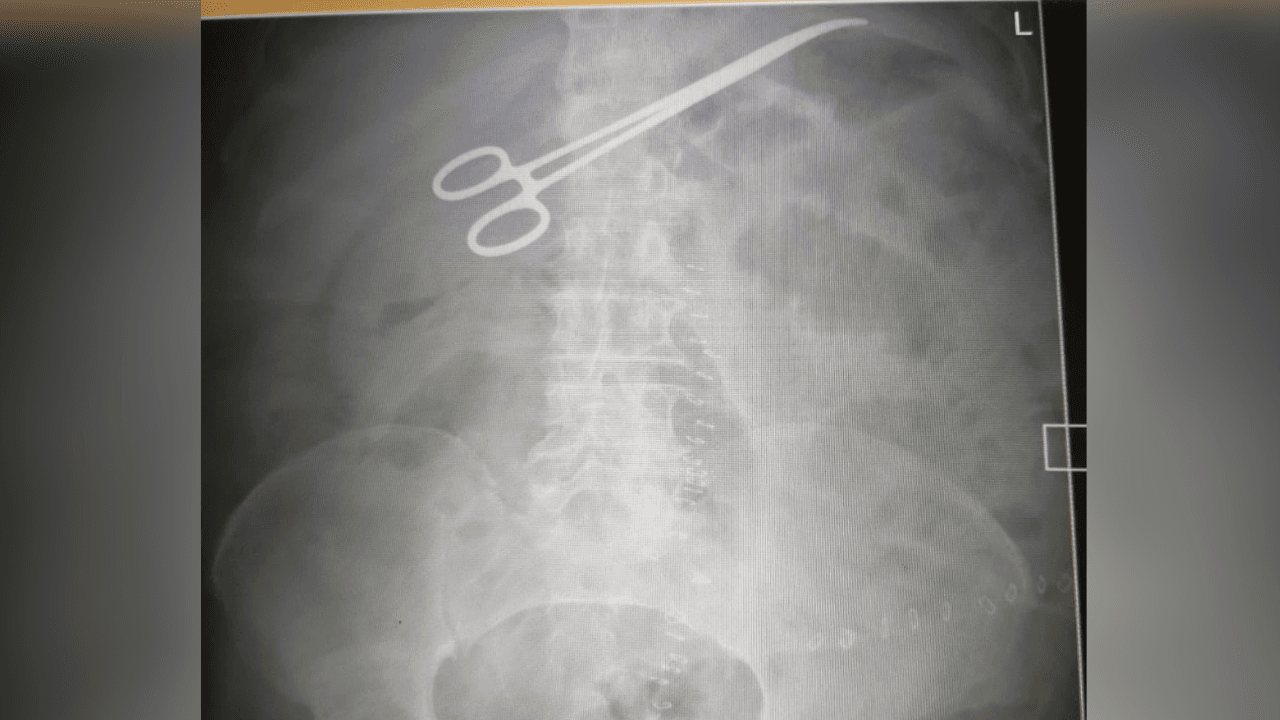

اتهامات ونفي وتحقيق رسمي.. "العبدلات" يكشف تفاصيل ما جرى في غرفة عمليات البشير

صورة أشعةالأربعاء، 26-11-2025